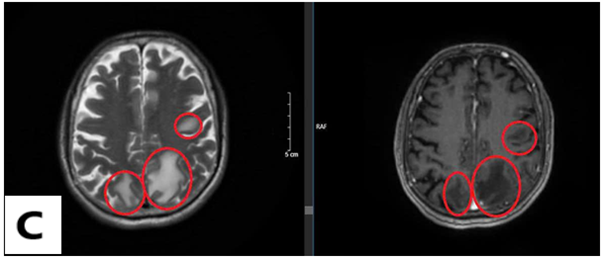

Hình ảnh chụp cắt lớp vi tính lồng ngực sau 3 chu kỳ điều trị hóa chất:

Trước điều trị

Sau điều trị

Hình 3: Hình ảnh chụp cắt lớp vi tính lồng ngực trước và sau điều trị

Nhận xét: Trước điều trị hóa chất thùy dưới phổi trái có khối tỷ trọng ngấm thuốc, thượng đòn phải và trung thất có vài hạch, nhóm 2, 4 bờ rõ, ngấm thuốc sau tiêm, các hạch dọc động mạch chủ bụng ngấm thuốc, tuyến thượng thận trái dày thân tuyến, tuy nhiên sau điều trị hóa chất 3 chu kỳ, không thấy hình ảnh khối tỷ trọng ở phổi, các hạch ở trung thất, thượng đòn, dọc động mạch chủ bụng cũng như hình ảnh dày thận tuyến thượng thận.